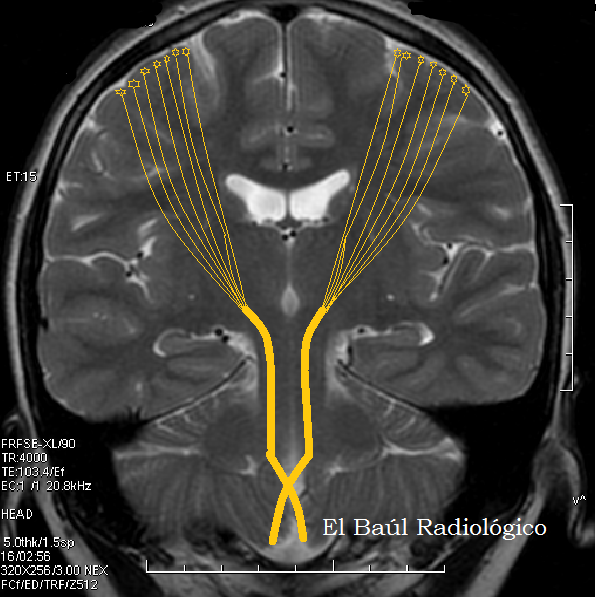

El Baul Radiologico Esclerosis Lateral Amiotrofica Hallazgos En Tomografia Por Resonancia Magnetica Amyotrophic Lateral Sclerosis Mri Findings By Luis Mazas Artasona Junio 2014

El Baul Radiologico Esclerosis Lateral Amiotrofica Hallazgos En Tomografia Por Resonancia Magnetica Amyotrophic Lateral Sclerosis Mri Findings By Luis Mazas Artasona Junio 2014 from 1.bp.blogspot.com